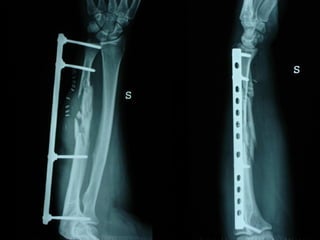

Dal Gennaio 2000 al Febbraio 2006 abbiamo trattato 167 fratture chiuse  con placca percutanea  in 164 pazienti :  27 lesioni diafisarie di gamba, 12 piloni tibiali ,  11 fratture prossimali di tibia, 36 fratture sovracondiloidee di femore, 17 fratture diafisarie di femore, 43 fratture metaepifisarie prossimali di omero, 21 diafisarie d’omero.  156 guarigioni 8 fallimenti

Dal Giugno 2002 al Dicembre 2004 abbiamo trattato 5 fratture esposte: 3 di tibia e 2 di ulna 5 guarigioni

I buoni risultati ottenuti dipendono da 5 punti fondamentali:   una accurata riduzione percutanea della frattura  precise vie di accesso  l’utilizzo della placca che consenta il più lungo braccio di leva possibile il pretensionamento della placca  una sintesi con un ridotto numero di viti

Precise vie di accesso

Placche lunghe e pretensionate

Placche lunghe e pretensionate Sintesi con un ridotto numero di viti

Fratture  esposte